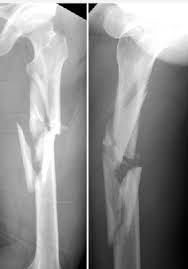

simple fracture

bone breaks but doesn't pierce the skin

compound fracture

bone breaks and pierces the skin

comminuted fracture

bone shatters into small pieces

spiral fracture

caused by twisting; break at an angle

epiphyseal fracture

break at the growth plate; epiphysis separates from diaphysis